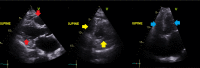

A pandemic outbreak of a novel coronavirus disease (COVID-19) that began in Wuhan, China, in December 2019 has spread rapidly to multiple countries. In the United States, the first confirmed case was reported on January 20, 2020, and since then, the number of cases is rising exponentially on a daily basis. We report a case of COVID-19 infection that presented with symptoms suggestive of pneumonia. Due to the major backlog with an immense number of pending tests, it took 48 hours for the result to come back positive, while the patient went into acute respiratory distress syndrome. We provide an internist's perspective of the difficulties encountered in terms of the available management options, as the patient progressively deteriorated on the regular medical floor prompting transfer to the intensive care unit.